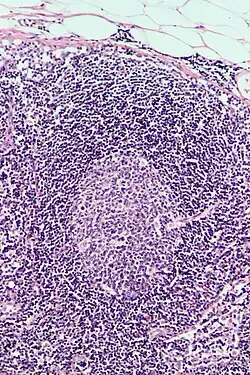

List of immune cells

This is a list of immune cells, also known as white blood cells, white cells, leukocytes, or leucocytes. They are cells involved in protecting the body against both infectious disease and foreign invaders.[1]